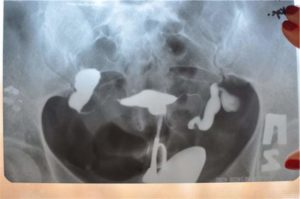

В этих случаях заподозрить заболевание и проверить проходимость просвета маточных труб позволяет гистеросальпингография с рентгенконтрастным веществом, вводимым в полость матки. Более точным считается метод гидросонографии, то есть проверка проходимости посредством ультазвукового исследования с одновременным введением стерильного раствора.

º Гистеросальпингография. Рентгеновская картина может быть как при непроходимости маточных труб, а если сактосальпинкс вентильный, контрастное вещество заполняет трубу, и она выглядит как извитая «колбаска».

Гидросальпинкс (сактосальпинкс) обычно диагностируют с помощью гистеросальпингографии (ГСГ).

Это рентгенологическая процедура, при которой рентгенконтрастную жидкость вводят в полость матки и оценивают форму матки и проходимость маточных труб. Если трубы не проходимы, то жидкость скапливается в трубе.

При проходимости маточных труб жидкость из конечного отдела труб выливается в брюшную полость.